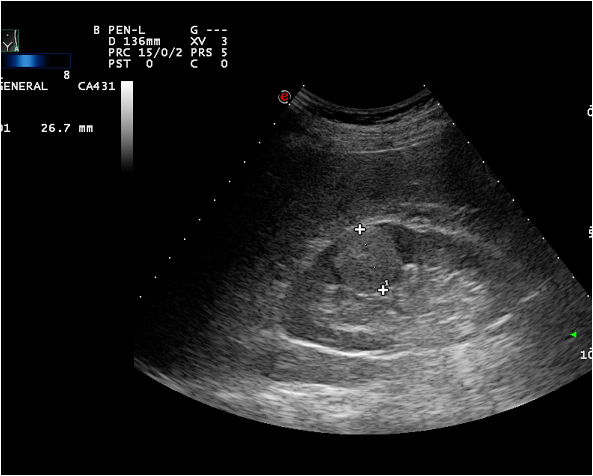

Ultrasonography (US), which is an extensively used and a widely available method, is often the first step in the diagnostic work up. During a regular abdominal US scan both kidneys are examined. Sensitivity of the US examination is significantly lower than of a CT scan, still important clinical questions can be answered with this technique. When a tumor is visualized, it is usually a hypoechoic, relatively well circumscribed mass.

Diagnostics of cystic lesions is based on the Bosniak classification system, which categorizes cystic lesions by their density, calcifications, wall thickness, contrast enhancement, surface lobulation and characteristics of the cyst contents.

Image

Figure 3. Kidney tumor on US